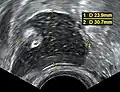

Dermoid cyst in vaginal ultrasonography